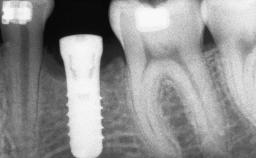

A 20-year-old woman was referred for implant therapy in 2004. Her medical history revealed no significant findings, and neither did she smoke nor take any medications. An extraoral examination revealed no abnormalities of the skin, hair or nails. The intraoral examination revealed only 11 permanent teeth clinically. These were normal in shape, size, and color. In addition, eight retained deciduous teeth (53, 62, 63, 71, 72, 73, 81, 82) were present. No abnormalities were detected during the general examination. The family history revealed that the patient’s father and two sisters were on record with similar conditions. The clinical examination revealed a thick gingival biotype. No recession of the attached gingiva was noted, but the retained deciduous teeth were mobile and unsightly. As a syndrome had not been diagnosed, the case was categorized as non-syndromic oligodontia.

Bone Augmentation Horizontal|Staged

Augmentation Materials Autogenous chips|Autogenous block(s)|Membrane

Bone Volume Deficient horizontally, requiring prior grafting